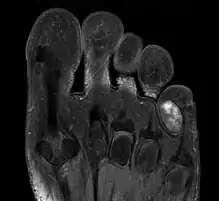

1. IRM d'un chondrome extérieur sur un petit doigt de pied.

Celui-ci se présente à l'extérieur ou l'intérieur des os d'articulation (doigts, genou, épaule) parfois sur des côtes et le sternum et les clavicules. S'y ajoute aussi le bassin.

Cependant pour le kyste malin, chondrosarcome , on en distingue la malignité par la biopsie et son évolution en cancer en général est suivable avec la radiographie le pet-scan et l'IRM[1].